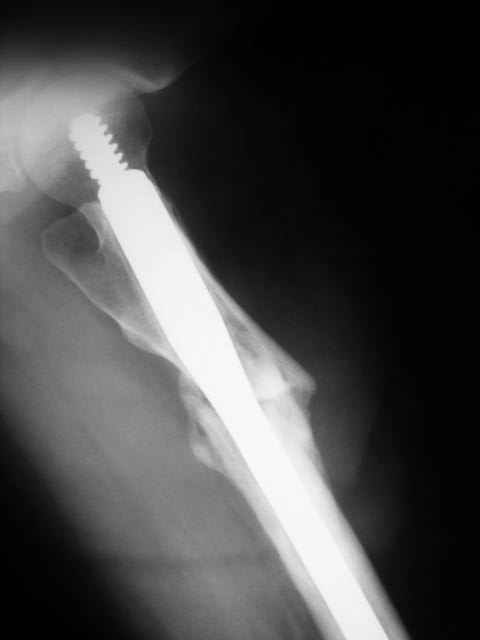

Advice on this case would be appreciated. 59 year old female normal body weight and nonsmoker.

Now 11 months out from initial fixation. No clinical evidence of infection. Closed fracture initially. CT confirms minimal bridging bone. Weightbearing pain in proximal thigh. My initial thought was onlay autogenous bone graft with BMP supplementation and leaving fixation as is. Any benefit to revision fixation and if so what implant? Her ROM and length are symmetric. Thanks.

No obvious sign of loosening so could do ipsilat PICBG with packing of nonunion, decortication and onlay graft. No need for BMP if autograft used. Probably would work.

Patient must have some micromotion given pain and radiographs, and more reliable would PICBG and revise fixation to more stability w/ Prox femoral locking plate, Blade plate or DCS depending on what you have experience with.

If the nail was dynamized I would consider exchange nailing with more medial entry point to provide more valgus position.

well done gamma nailing,

did you try to dynamise the nail?

Re-nailing maintains the same axial alignment; she probably needs axial correction and a classic blade-plate, with compression and ICBG. Save the money and do not buy BMP’s…